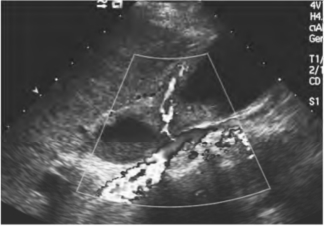

2.彩色多普勒超声表现 病变区域有血供增多的特点(图25-11),频谱多普勒可发现高速的动脉血流。

图25-11 胆囊癌二维与彩色多普勒超声图(见彩图36)

彩色多普勒显示胆囊癌病变区域血供增多